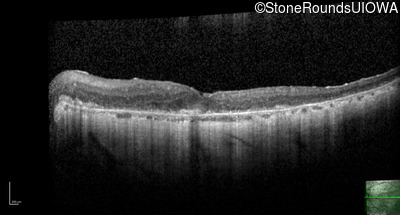

Optical Coherence Tomography - Left - 20/80 -1

Exemplar / OCT Stack